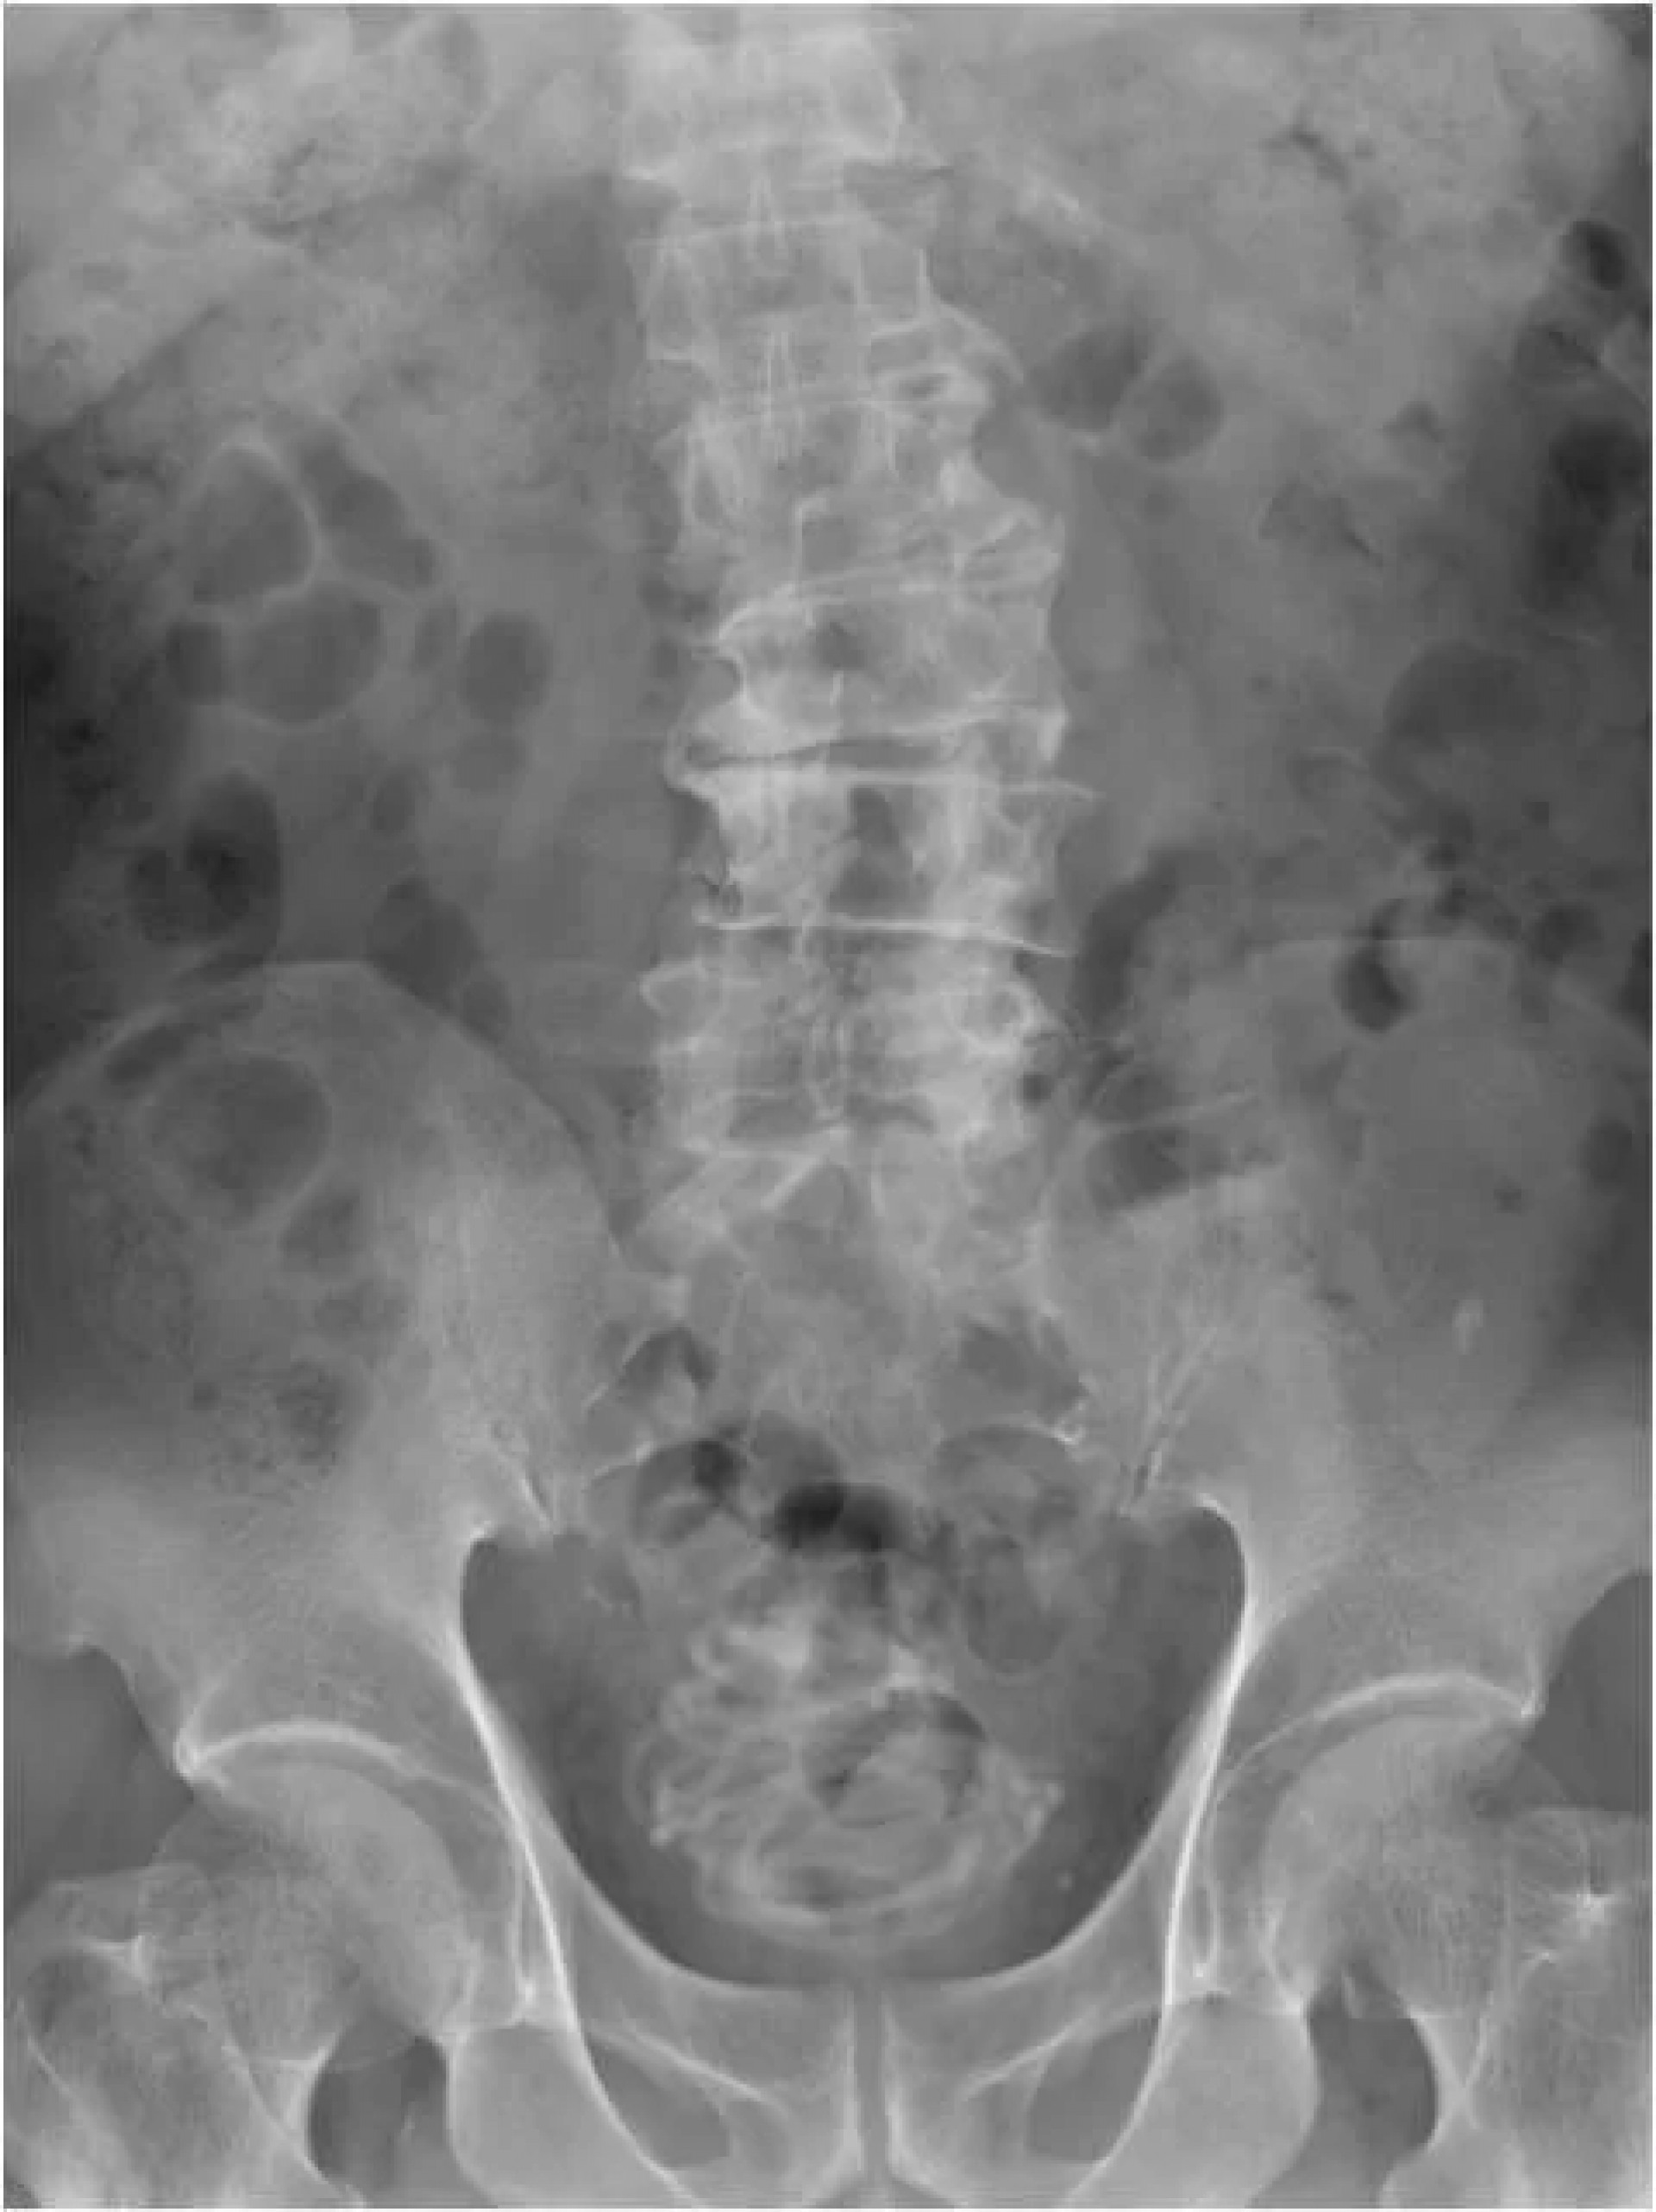

“Primeiro realizamos um ultrassom e identificamos um objeto grande na bexiga do paciente. Depois fizemos um raio-x, que revelou um corpo estranho enrolado em forma de fio", detalhou Toshiki Kijima, autor do relatório publicado na revista médica.

Depois do exame, a equipe fez uma tomografia do paciente para escolher o melhor jeito de tirar a corda. "Usamos um programa de computador em 3D para nos direcionar pois percebemos que seria impossível puxar a corda pelo pênis”, afirma Toshiki.